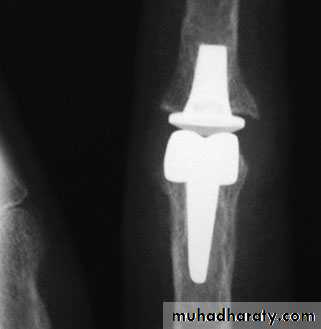

Wrist replacement